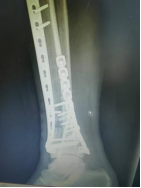

4.胫腓骨粉碎性骨折—MIPO技术